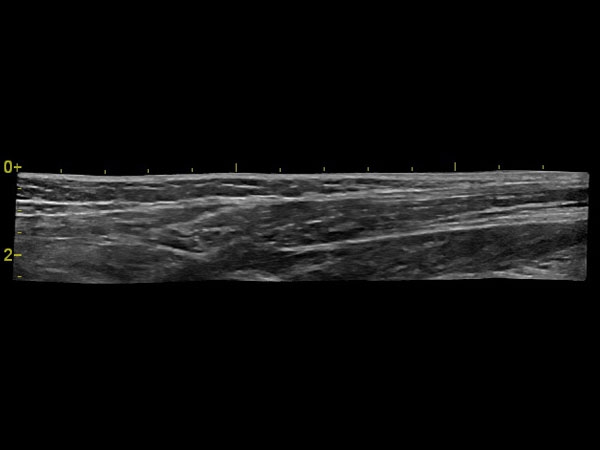

• скелетно-мышечная система;

Панорамное сканирование:

Да